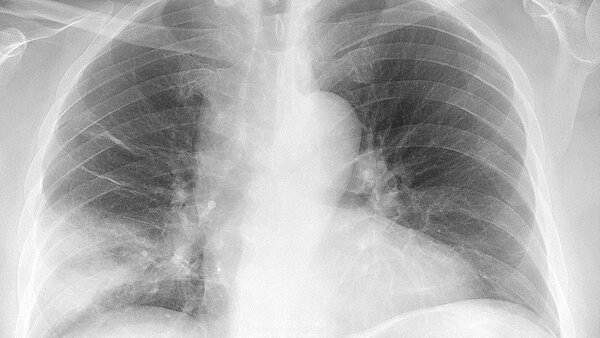

2. Пневмония

Фото © Wikimedia Commons / Mikael Häggström

В постельном белье живёт и кое-кто поопаснее пылевых клещей, например стафилококк. Эта бактерия может вызвать пневмонию — болезнь, которая приводит к проблемам с дыханием и, в тяжёлых формах, даже к смерти.

Врачи называют пневмонию "тихой убийцей", потому что её симптомы на ранних стадиях напоминают обычную простуду.